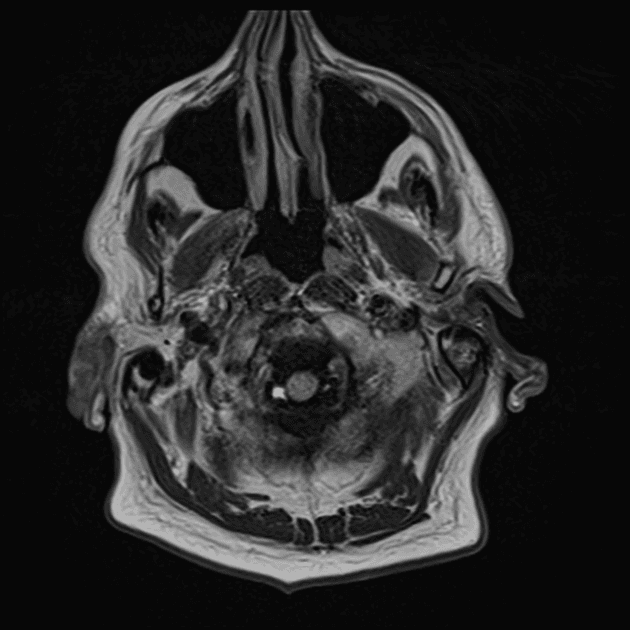

Chụp cộng hưởng từ (MRI) cho thấy các đặc điểm điển hình của bệnh xơ cứng rải rác. Ngoài ra, một số tổn thương có tín hiệu tăng trên hình ảnh T1 (T1 hyperintense).

- Các tổn thương rải rác, dạng vệt hoặc hình tròn, tăng tín hiệu trên hình ảnh khuếch tán (diffusion-weighted imaging), khu trú chủ yếu ở vùng chất trắng quanh thất (periventricular white matter), chất trắng ở bán nguyệt (juxtacortical white matter), thân gai thị – giao thoa thị giác (optic radiation – optic chiasm), và thân não (brainstem) – phù hợp với đặc điểm của xơ cứng rải rác (multiple sclerosis).

- Một số tổn thương có tín hiệu tăng trên T1 (T1 hyperintense lesions) – gợi ý tổn thương mạn tính, liên quan đến mức độ tàn phế tăng và teo não (atrophy).

- Thể chai (corpus callosum) có tổn thương dạng dải ngang (Dawson's fingers) – đặc trưng của xơ cứng rải rác (multiple sclerosis).